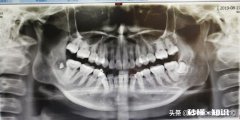

- 智齿离神经多远